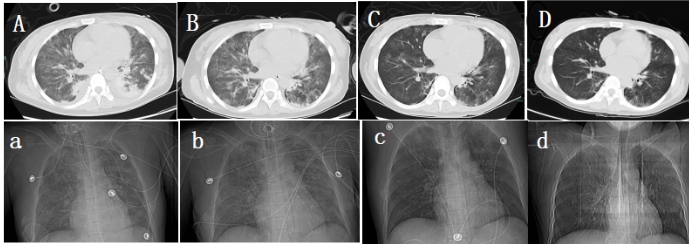

1.3.2 影像学检查2021-04-14彩色多普勒超声:右侧甲状腺下极下方低回声,大小2.3 cm×1.5 cm,边界清,甲状旁腺来源首先考虑(图 1A, B);双肾B超提示:双肾肿大伴肾病表现。2021-04-17颈部CT:右侧甲状腺后方结节(图 1C)。心脏超声:主瓣瓣环及二尖瓣瓣环及二尖瓣腱索上多发钙化,左室壁偏厚,肺动脉压增高。肺部CT:两肺炎症病变,两侧少量胸腔积液(图 2A)。

| A, a患者甲状旁腺腺瘤切除术前2021-04-13肺部CT;B, b患者术后第3天2021-04-25肺部CT;C, c患者术后第10天2021-05-02肺部CT;D, d患者术后第25天2021-05-17肺部CT 图 2 转移性肺钙化治疗前后的胸部CT影像 |

2021-04-22患者在全麻下行右侧甲状旁腺腺瘤腔镜下切除术,术后病理报告:(右侧)符合甲状旁腺腺瘤。术后血清总钙2.45 mmol/L,甲状旁腺激素27.7 pg/mL, 停鲑降钙素肌肉注射治疗。CRRT设定血流量与枸橼酸钠泵速比为1∶1.3,监测血气分析调整静脉端补钙剂量,维持离子钙1.0~1.2 mmol/L范围,患者术后第2天经呼吸锻炼后脱机成功,气管切开处高流量吸氧。2021-04-25停止CRRT治疗。肺部CT:两肺炎症病变,较前吸收(图 2B, b)。2021-04-28停用抗生素治疗,改为鼻导管吸氧,开始床边坐起进行关节功能锻炼。2021-05-02肺部CT:两肺渗出性病变,较前明显吸收(图 2C, c),2021-05-09患者转康复病房进行肺功能训练、平衡功能训练、关节功能锻炼、中药辅助治疗。2021-05-17复查肺部CT:两肺渗出性病变,较上次明显吸收(图 2D, d)。2021-05-26血气分析:PH 7.37, 乳酸0.60 mmol/L,二氧化碳分压31.70 mmHg, 氧分压117.00 mmHg(1 mmHg=0.133 kPa), 氧饱和度100%(吸入氧流量21%),标准碳酸氢盐19.2 mmol/L。肾功能:肌酐104 μmol/L,肾小球滤过率61 mL/min,血清钙1.93 mmol/L。双上肢肌力5-级,双下肢肌力4+级,坐位平衡3级,立位平衡2级,2021-05-28患者要求出院回当地继续康复治疗。

pHPT伴MPC快速进展案例较为罕见,研究[5]表明原发性HPT伴高钙血症、原发性HPT、高钙血症和继发性HPT伴肾功能衰竭、维生素D缺乏症、骨髓瘤等疾病是MPC的危险因素,能否有效控制高钙血症和高PTH是治疗的关键。本例患者采用含钙1.50 mmol/L的置换液进行RCA-CRRT联合鲑降钙素降钙治疗,为进一步诊断及手术治疗赢得了时间,患者在切除右侧甲状旁腺腺瘤病灶后,肺钙化症状明显改善(图 2D, d),表明pHPT伴MPC手术治疗后有逆转的可能。